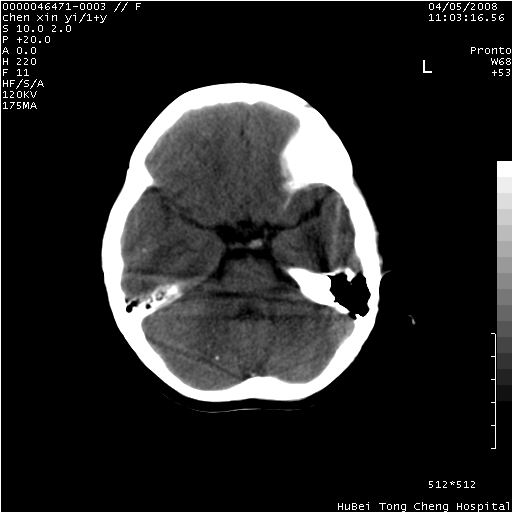

以下是引用zhangzhongshou在2008-4-9 12:54:00的发言:[br]请结合病史,有以下可能1、炎性肉芽肿钙化(含结核)2、寄生虫钙化(含脑囊虫)3、其他良性钙化性病变